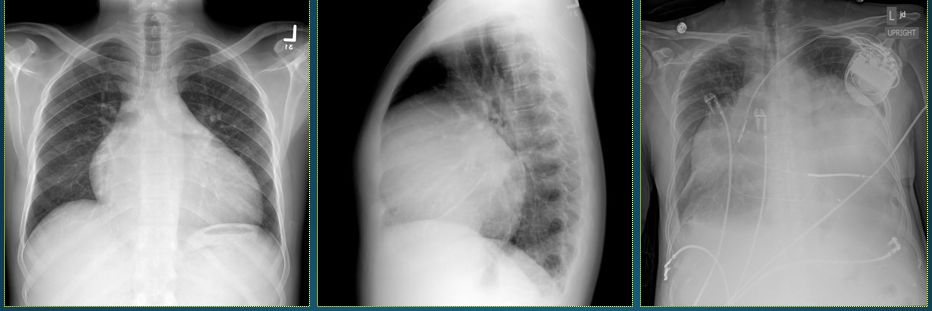

球形心

气球心

球形心:房室普遍增大,器质性心脏病晚期(也见于新生儿,小儿心脏x片).

2-1 普大型心,左右心房,心室均扩大,肺动脉段平直

心脏x线表现

可以从胸片上来诊断,比如在胸片上可以看到类似球形心的改变.